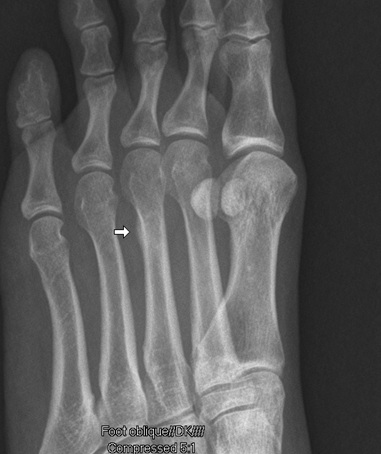

Met Fracture Blog #2

Oblique X-Ray view with small right arrow showing irregularity at Metatarsal #3.